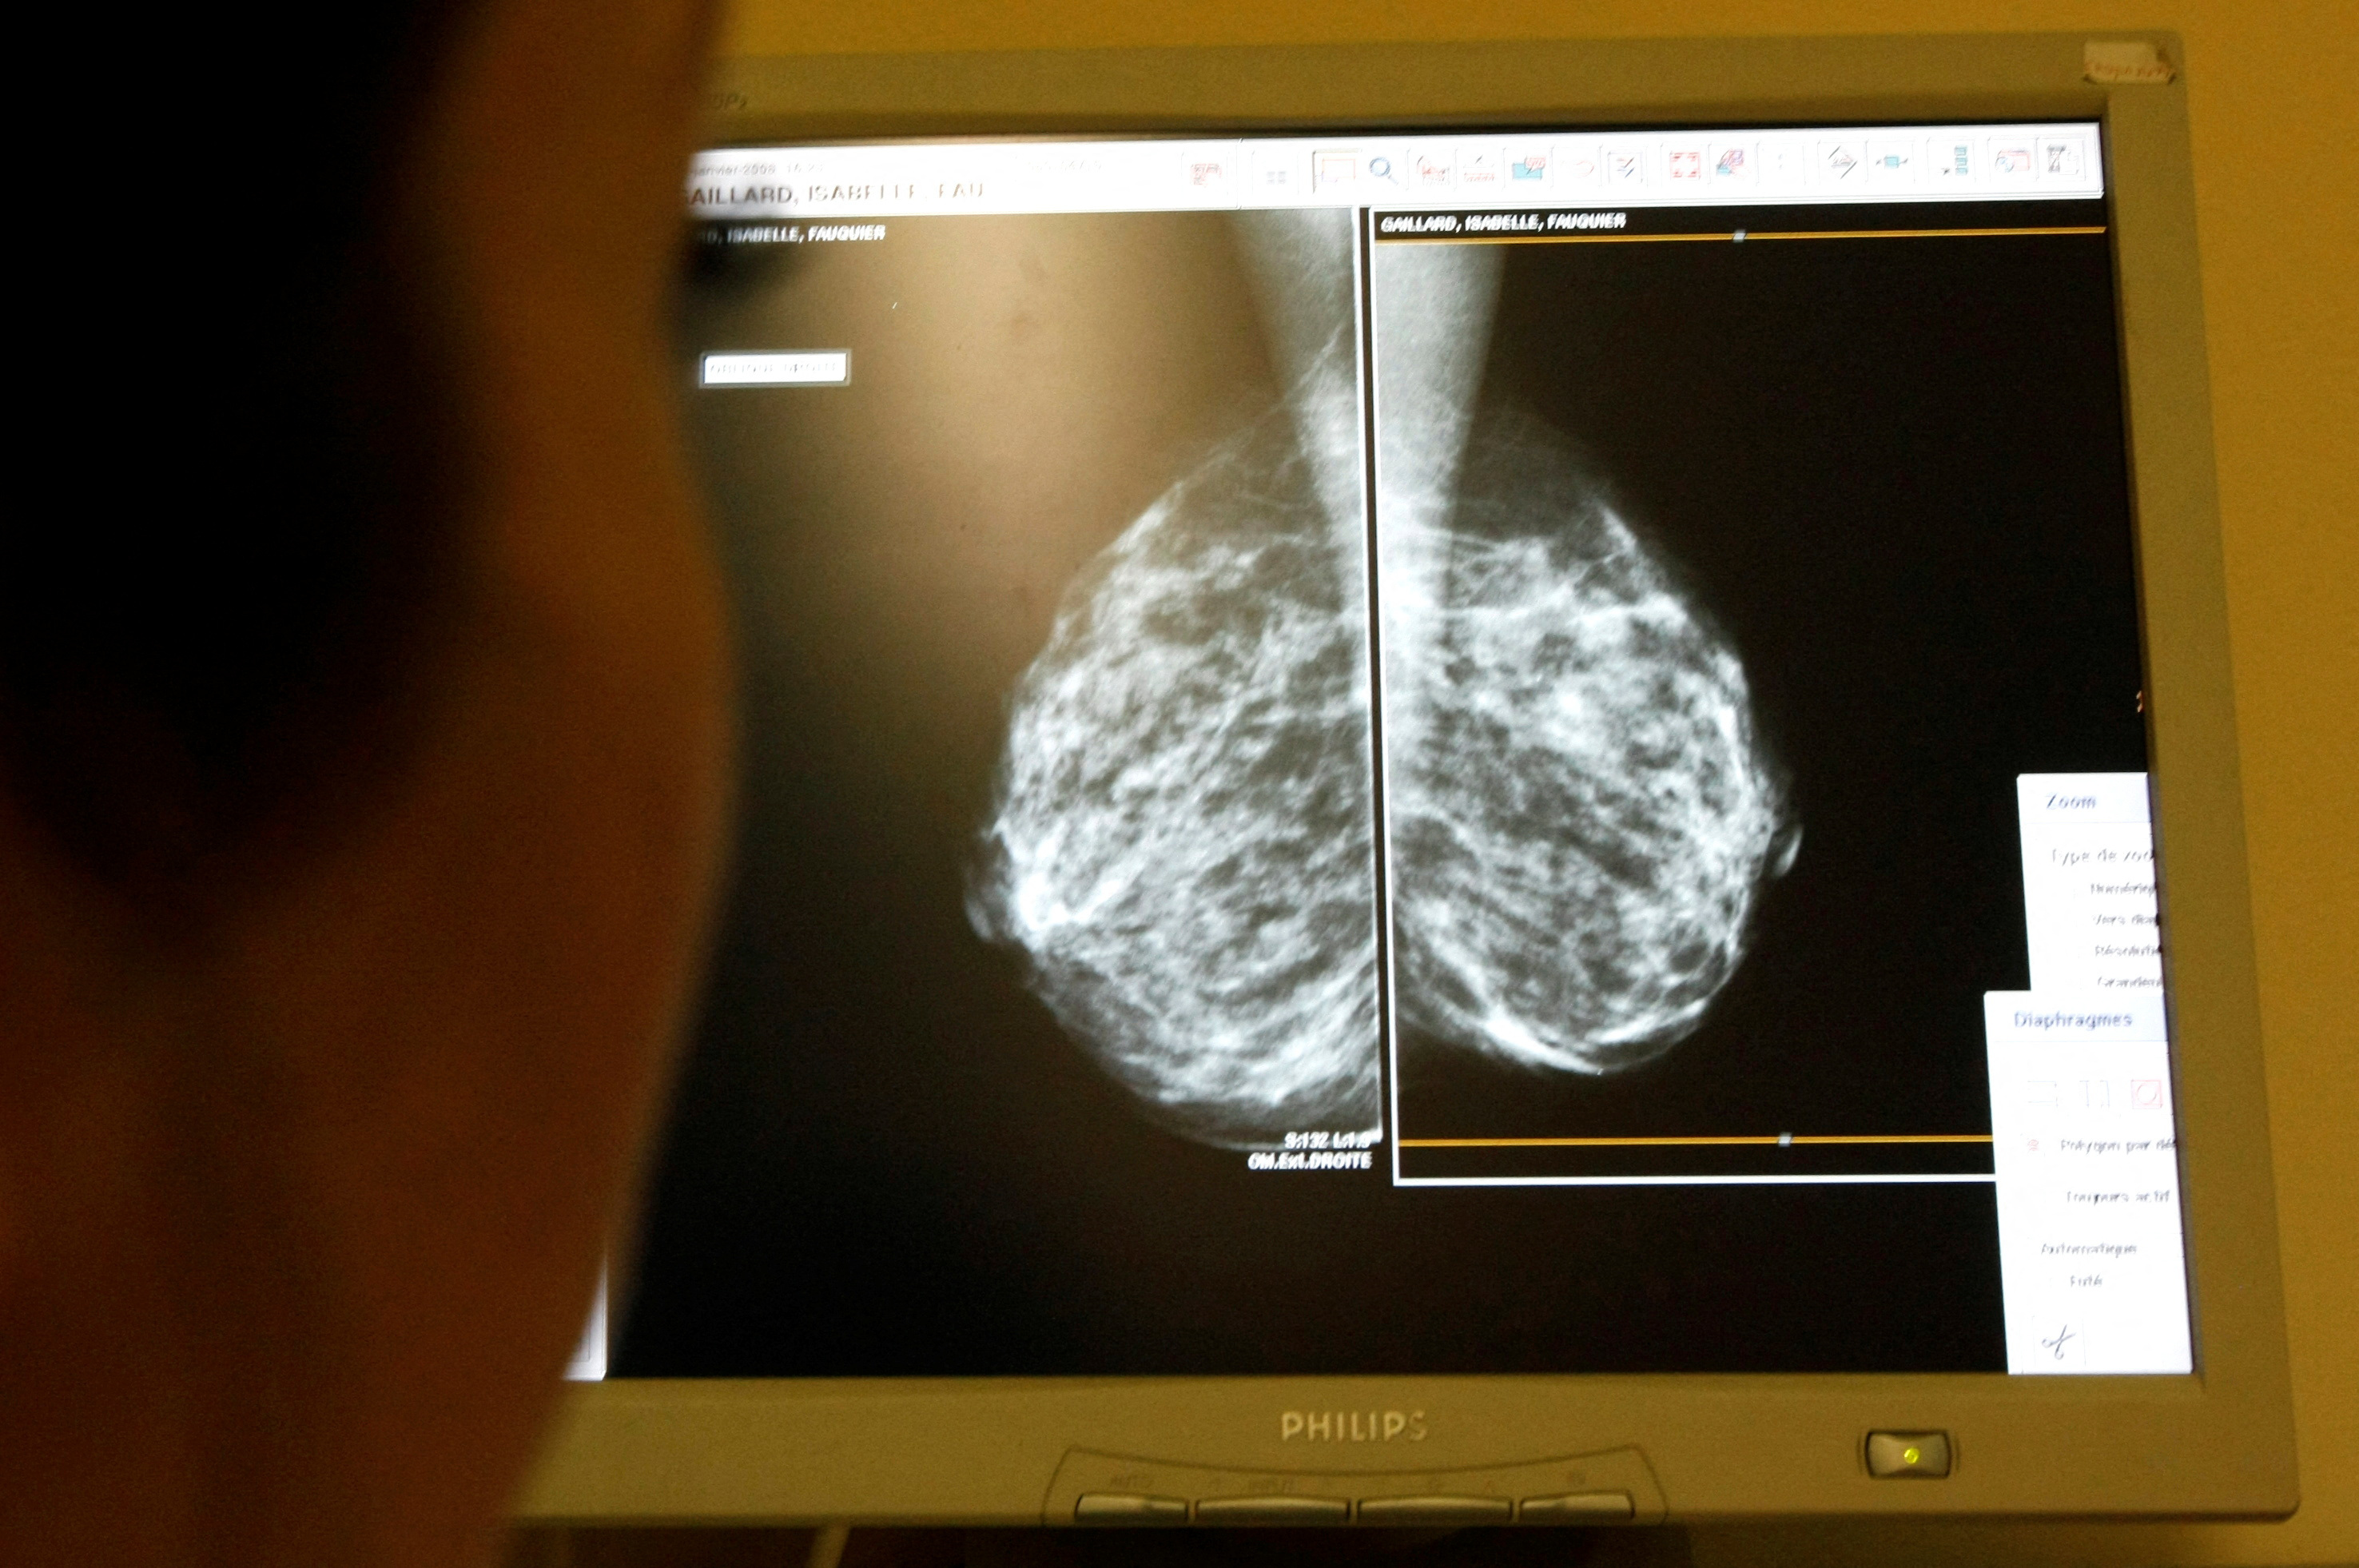

Utvrđeno je da, osim raka crijeva, rastu i slučajevi raka štitnjače, multiplog mijeloma, jetre, bubrega, žučnog mjehura, gušterače, sluznice maternice (endometrija), usne šupljine, dojke i jajnika.

Rak crijeva i dojke najčešći su među mlađim odraslima, s oko 11.500 slučajeva godišnje, dok su rak gušterače i žučnog mjehura znatno rjeđi. Samo rak crijeva i jajnika rastu isključivo među mladima, dok ostalih devet raste i u starijim dobnim skupinama.